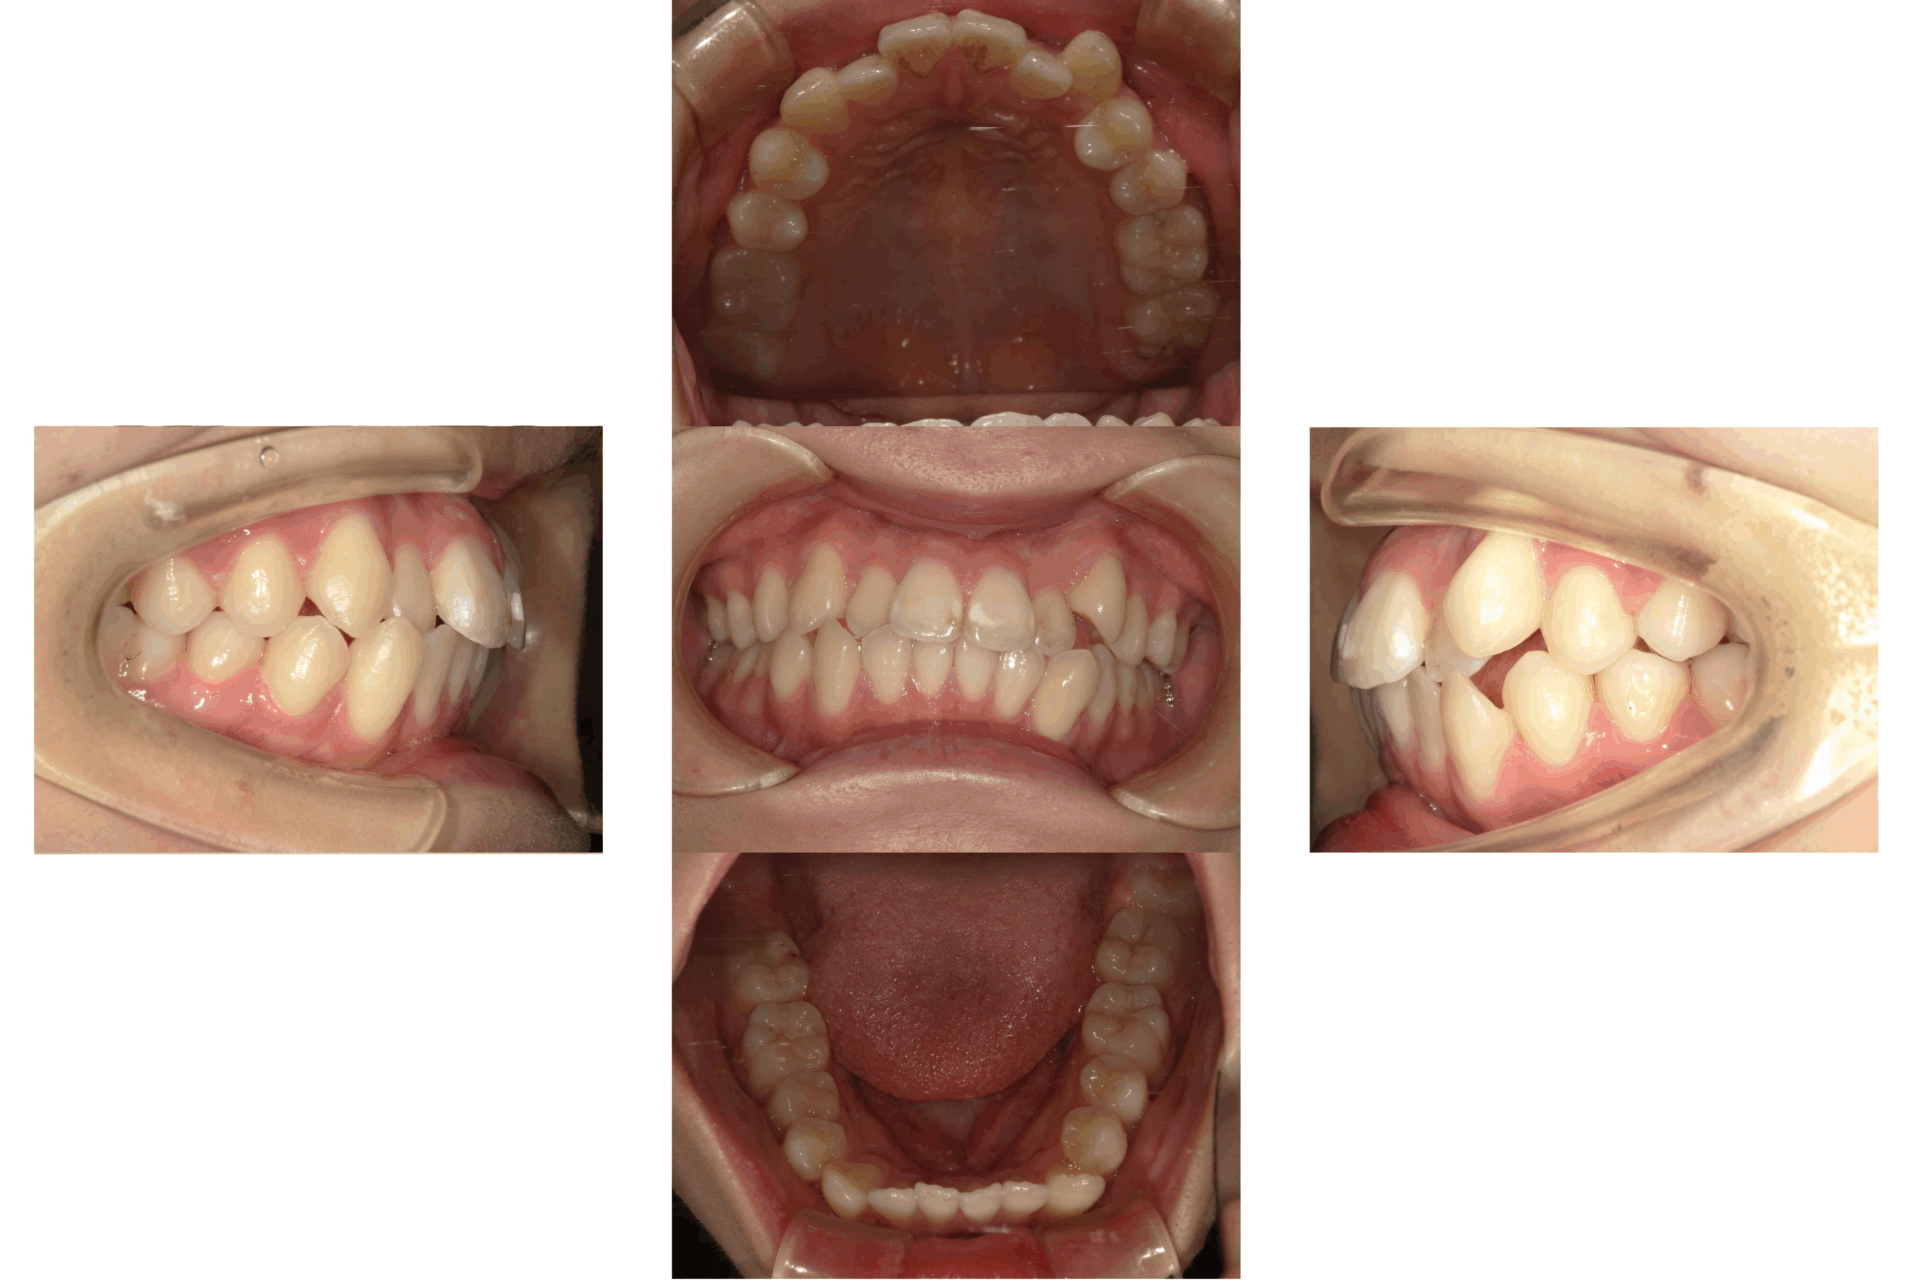

20代、女性、ワイヤー

| 施術内容 | 主訴:口ゴボが気になる。 詳細:ワイヤー矯正での歯並び改善 上下左右4抜歯 口元がかなり変化し、とても満足された症例です。 |

| 治療期間 | 20ヶ月(2/16現在 治療終了) |

| リスク・副作用 | ■リスク・副作用 ・治療の初期段階では、痛みや不快感が生じやすくなりますが、一週間前後で慣れます。 ・歯の動き方には個人差があるため、予想された治療期間より延長する場合があります。 |

| 費用 | ワイヤー矯正 60万円(税込660,000円) |